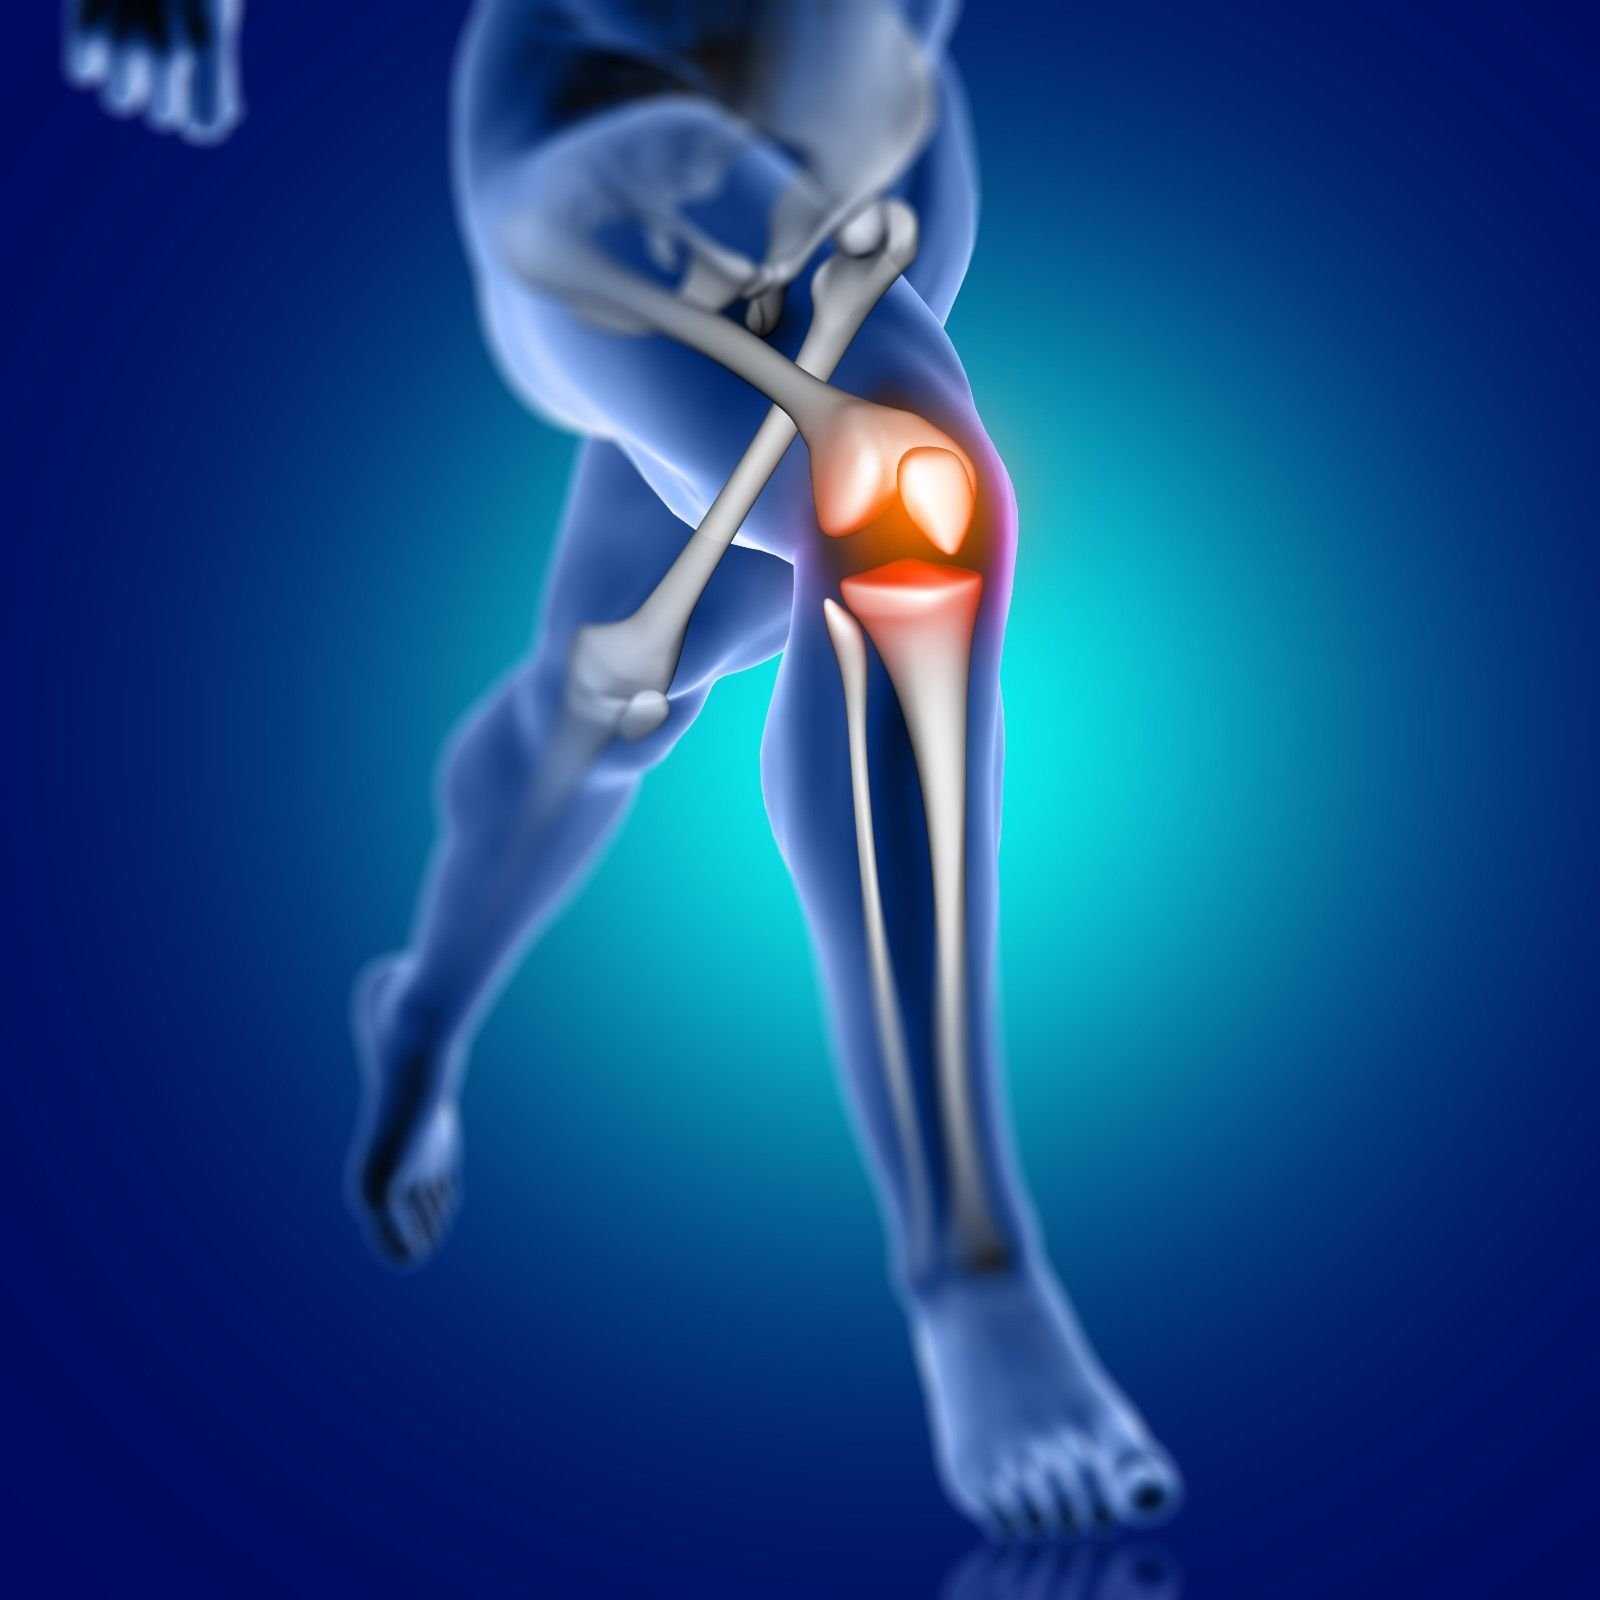

Knee Replacement, also known as knee arthroplasty, is a surgical procedure performed to replace damaged or worn-out knee joint surfaces with artificial implants. It is recommended for patients with severe knee pain, stiffness, and mobility issues caused by osteoarthritis, rheumatoid arthritis, injuries, or degenerative joint diseases.

Persistent knee pain affecting daily activities

Stiffness and swelling unresponsive to medications or physiotherapy

Severe joint damage due to arthritis or trauma

Reduced mobility and quality of life